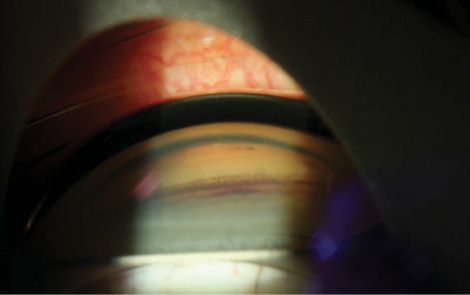

UGH syndrome and its close relative, secondary pigment dispersion syndrome, are most often associated with problems related to IOL implantation. UGH syndrome was first described in 1978 as an “intraocular chafing” with release of pigment and recurrent hemorrhage with an associated rise in IOP.2 The condition is usually caused by repetitive injury to the iris from a malpositioned lens implant’s optic or haptic.3 The most common sites of contact are the posterior iris pigment epithelium and the pars plicata. UGH syndrome is associated with excessive movement of the IOL or, in the case of old lens designs, with poorly fabricated edges or rigid, closed-loop haptics. The condition was first described with anterior chamber lenses but was eventually seen with malpositioned posterior chamber lenses as well.4 The risk is likely increased with systemic anticoagulation.5 Symptoms include decreased vision because of bleeding, pigment dispersion, or corneal edema. The problem waxes and wanes but can become permanent with optic nerve or corneal damage as well as nonclearing vitreous hemorrhage. Ocular signs include anterior chamber and vitreous hemorrhage, increased IOP, and typical glaucomatous optic neuropathy. There may be evidence of pigment dispersion in the angle and cornea (Figure 6) as well as transillumination defects of the iris (Figure 7). Corneal edema is caused by elevated IOP and, over time, can result in corneal blood staining. Chronic inflammation leads to signs of anterior uveitis and, eventually, cystoid macular edema.

Medical management includes topical steroids for inflammation and topical and oral glaucoma medications for lowering the IOP. Topical mydriatics are commonly used to control pain and reduce rubbing of the iris on the offending implant. Depending on the location of the IOL, miotics can alternatively be used to prevent contact. Dilated gonioscopy, ultrasound biomicroscopy,6 and intraoperative endoscopy are helpful for diagnosing the cause of the problem and planning surgical management. Most patients will require surgery to address the cause of the trauma. It may involve IOL rotation, partial or complete removal, or replacement with a sulcus-placed three-piece IOL or a scleral fixated or anterior chamber IOL.7 The intervention must be tailored to the specific type and location of the problem. Surgery to manage the glaucoma can involve angle-based microinvasive glaucoma surgery, endoscopic cyclophotocoagulation, or traditional glaucoma filtration surgery (trabeculectomy or aqueous tube shunt).